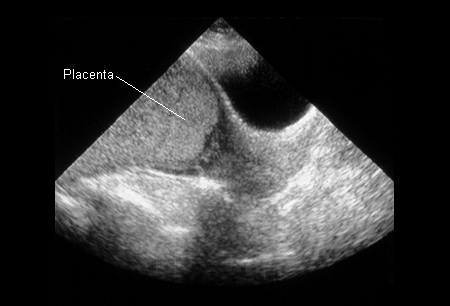

[Figure caption and citation for the preceding image starts]: Placenta prévia (anteriormente conhecida como prévia total) na 22ª semanaDo acervo de aulas de Janet R. Albers, MD [Citation ends].